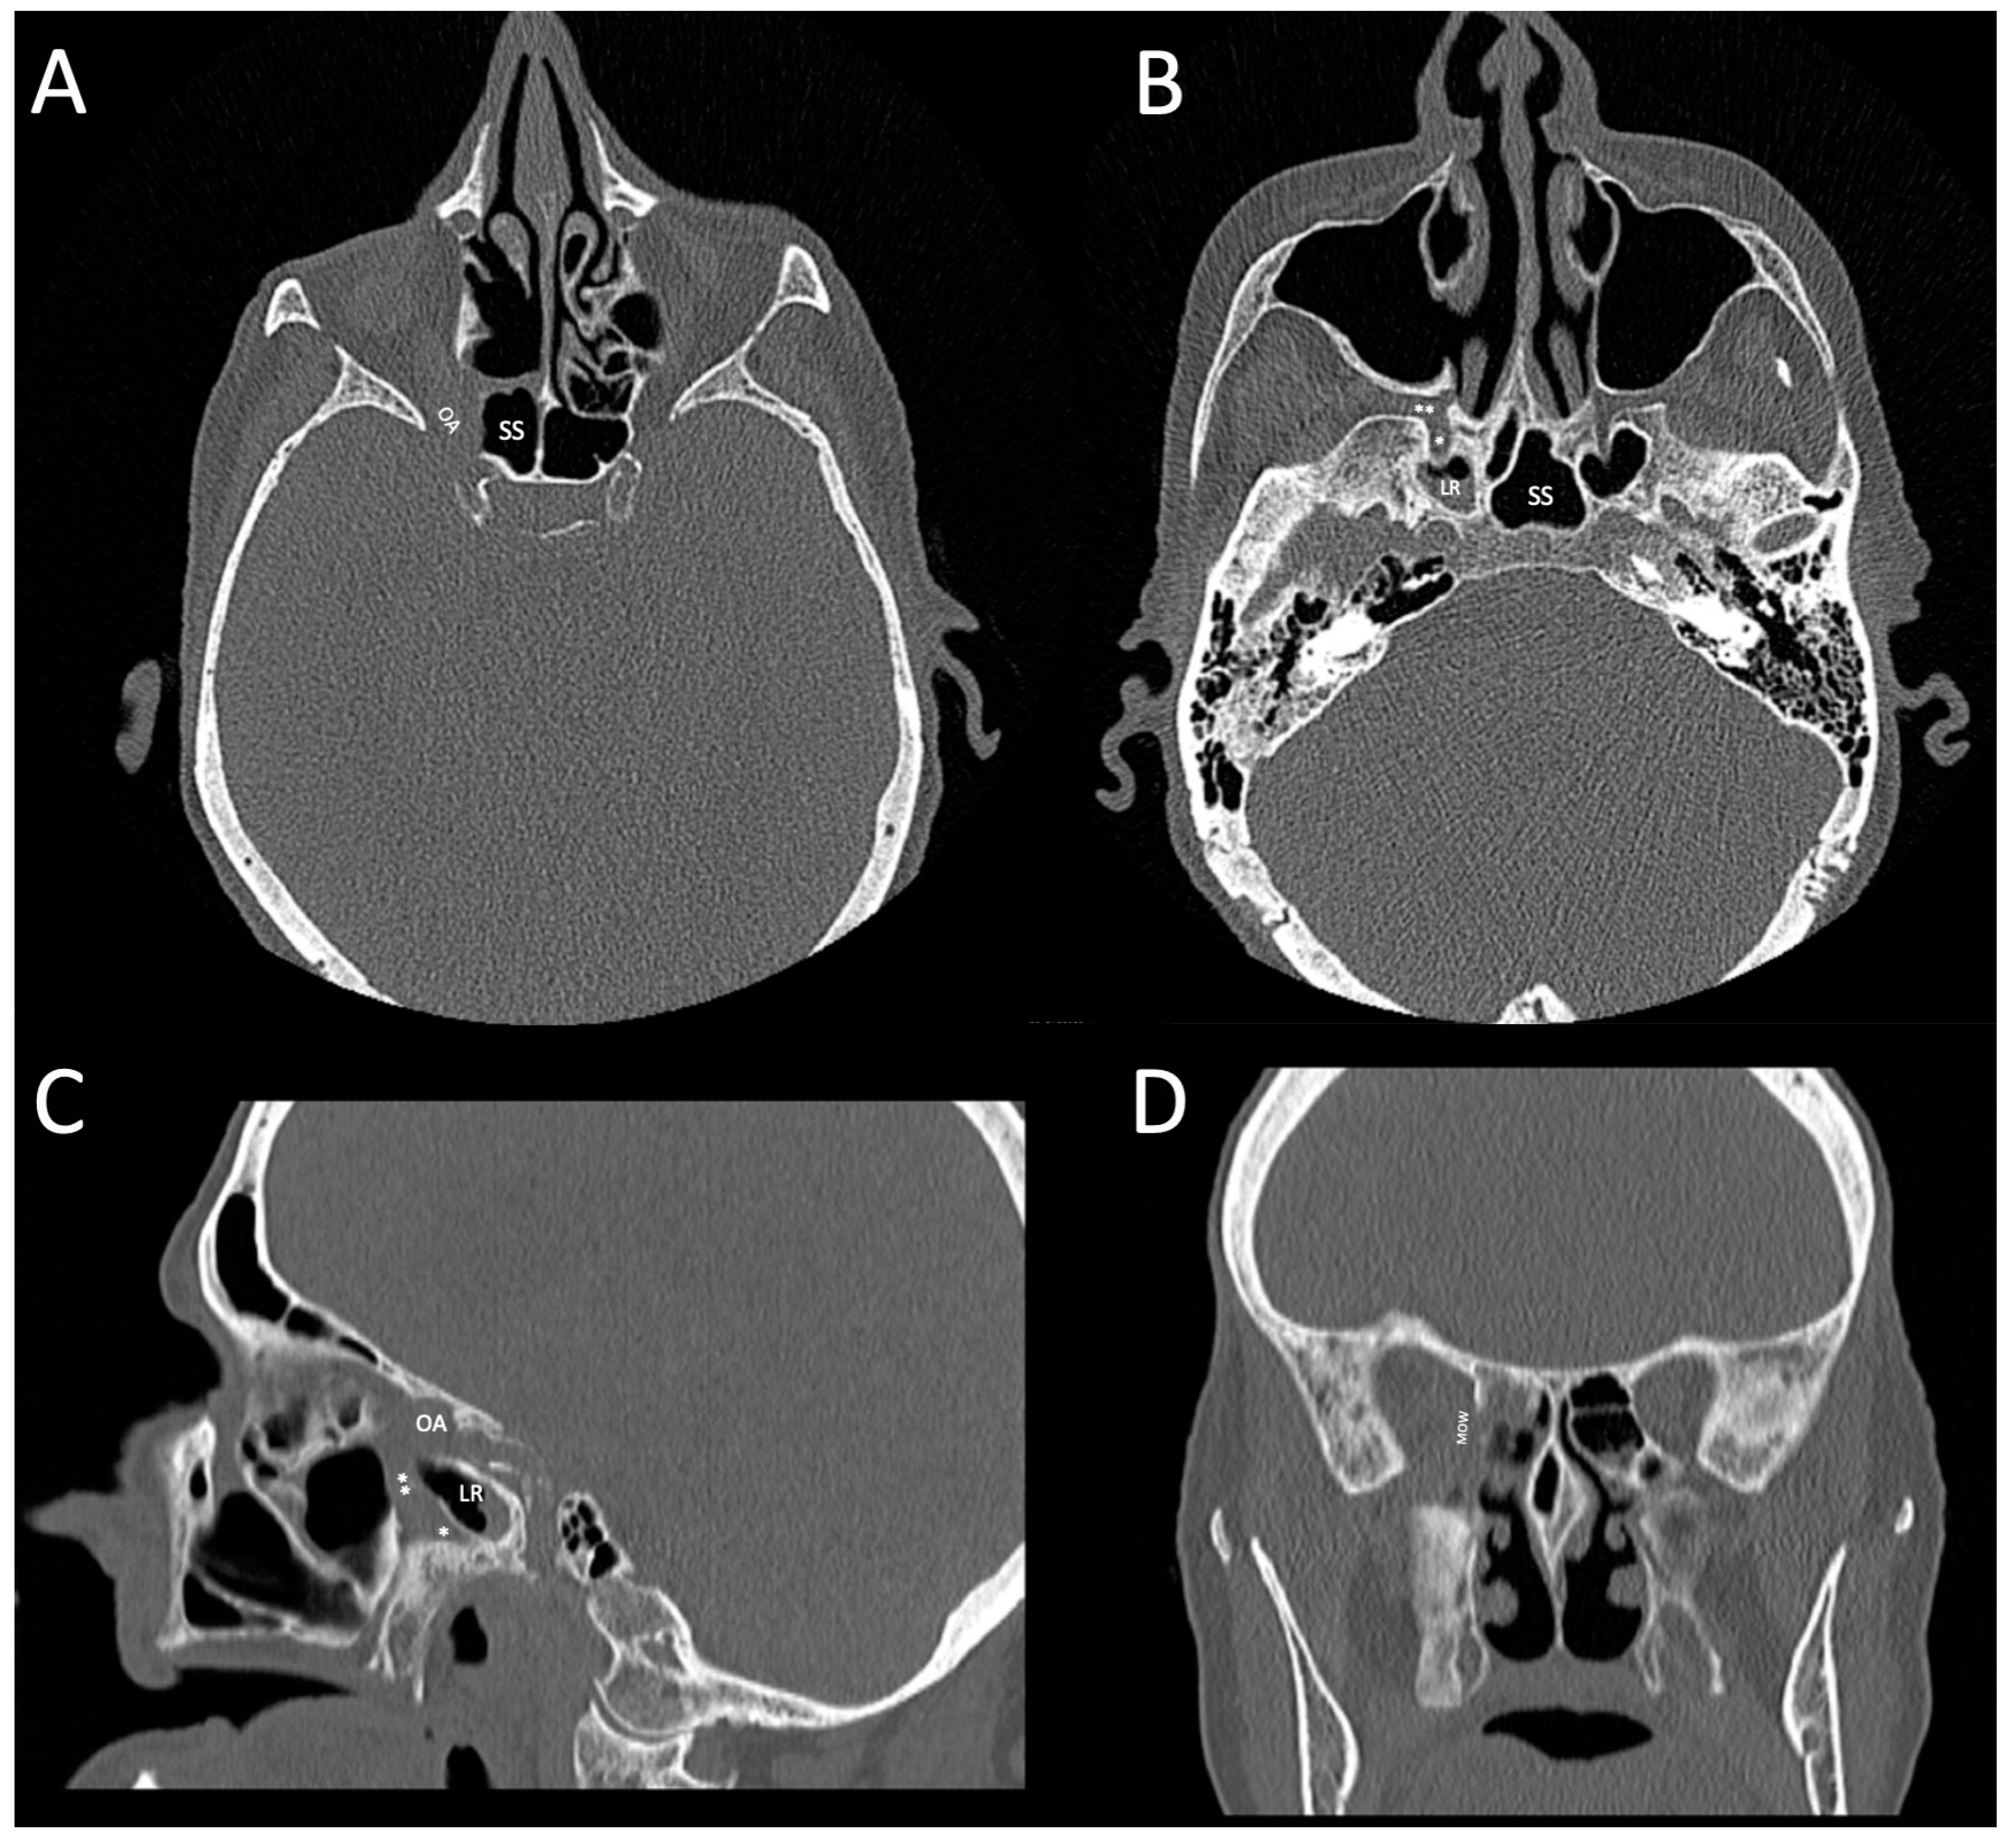

2. Case Presentation

2.1. Initial Presentation and Treatment

2.2. Revisional Treatment